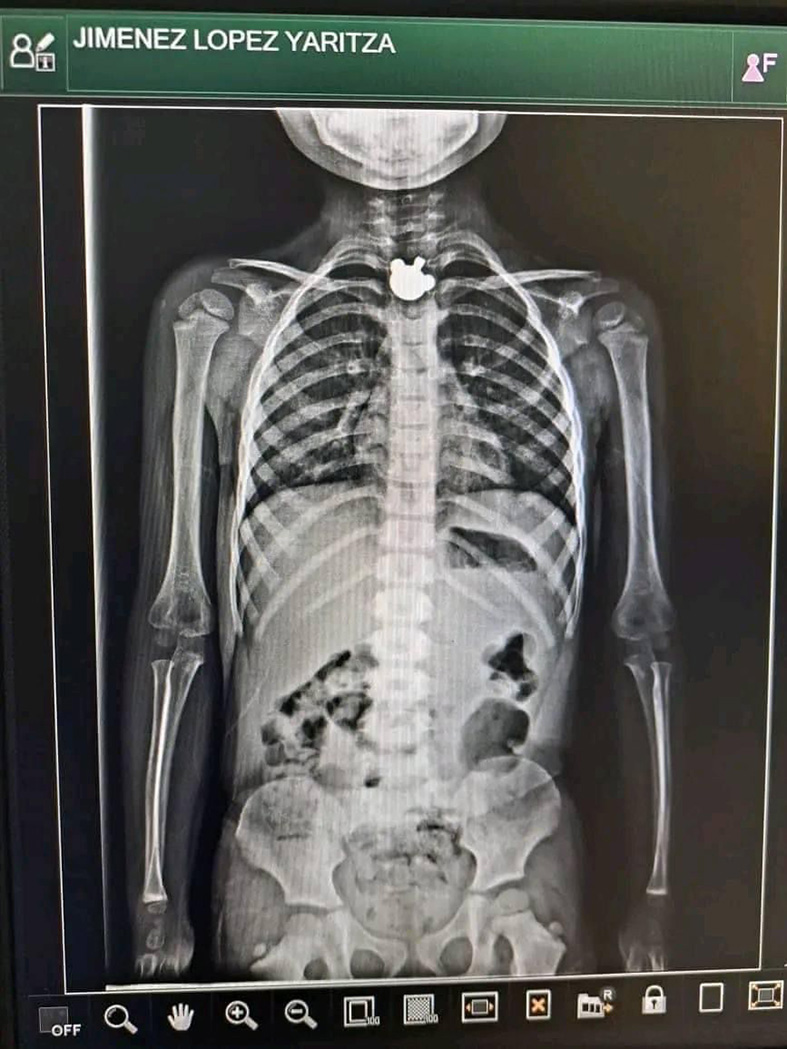

Una niña de nombre Yaritza “N”, originaria de Ocosingo, accidentalmente se tragó una figura de metal y de acuerdo a los resultados médicos, su vida está en riesgo, y que es difícil retirar el objeto.

Fue traída de emergencia al hospital de San Cristóbal, sin embargo, no pudieron hacer nada ya que la figura no se puede sacar por la vía de la boca.